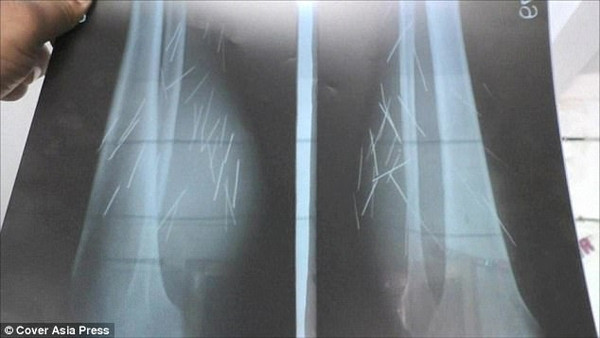

Mãi cho tới ngày 25/10, bác sĩ mới tìm ra được nguyên nhân. Sau khi chụp X quang, họ tá hỏa khi nhìn thấy có 70 vật nhọn bên trong đùi người phụ nữ.

Bác sĩ Naresh Vishal nói: “Cô ấy tới đây trong tình trạng rất đau đớn. Chúng tôi chụp X quang toàn thân cho Devi và phát hiện ra 70 mẩu kim loại trong chân, phần dưới đùi của cô ấy. Chúng tôi chụp toàn thân để xem liệu các mẩu kim loại có xuất hiện ở những bộ phận khác trên cơ thể không. Tuy nhiên, những mẩu kim loại đó chỉ có ở chân“.

Kỳ lạ người phụ nữ 'sản xuất' cả vốc kim, đinh nhọn trong chân ảnh 3Ảnh chụp X quang chân của Devi.